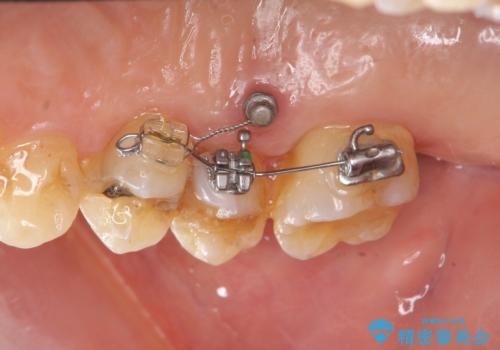

部分矯正を含む 歯周病治療 (再生治療・歯周ポケット除去・MTM・連結補綴)

検査の結果、強い歯ぎしりによる歯の周囲の骨の吸収が認められたため歯槽骨の再生・歯周ポケットの除去・力に対抗する連結補綴・補綴前処置としての小矯正を計画します。

今回連結補綴を行うにあたり、歯周病の問題を解決するために再生療法・歯周ポケット除去手術を、またより歯の神経を保存し力に対抗できる環境を整えるために小矯正を行い精度の高いメタルボンドクラウンを製作することができました。